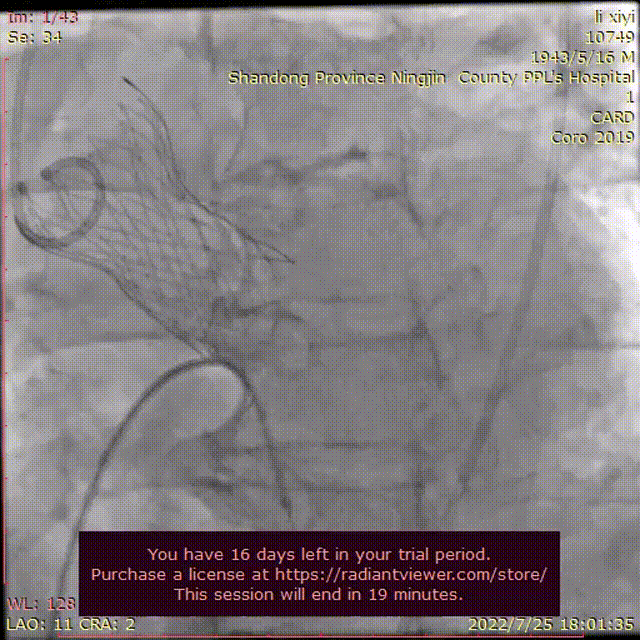

左冠脉造影

右冠脉造影